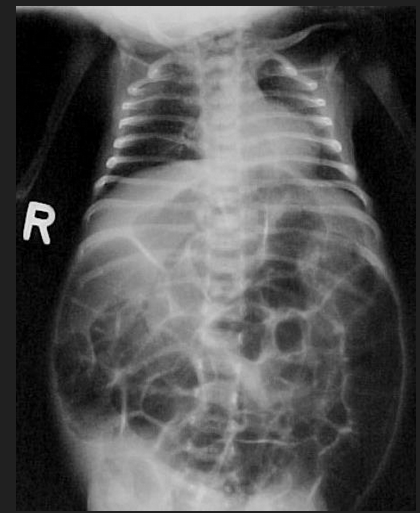

Loss of ganglion cells in both Meissner submucosal plexus and Auerbach myenteric plexus due to loss of Loss of ganglion cells in both Meissner submucosal plexus and Auerbach myenteric plexus

Hirschsprung Disease rectum (always) and sigmoid colon (often

A newborn infant has not passed meconium in 2 days and has bilious vommiting. Distended abdomen is appreciated on exam. During digital rectal examination, gas and stool is explused. Distended loops of bowel and an absence of gas in the rectum is seen on abdominal radiography.

•TX: Surgical resection of segment that lacks ganglion cells